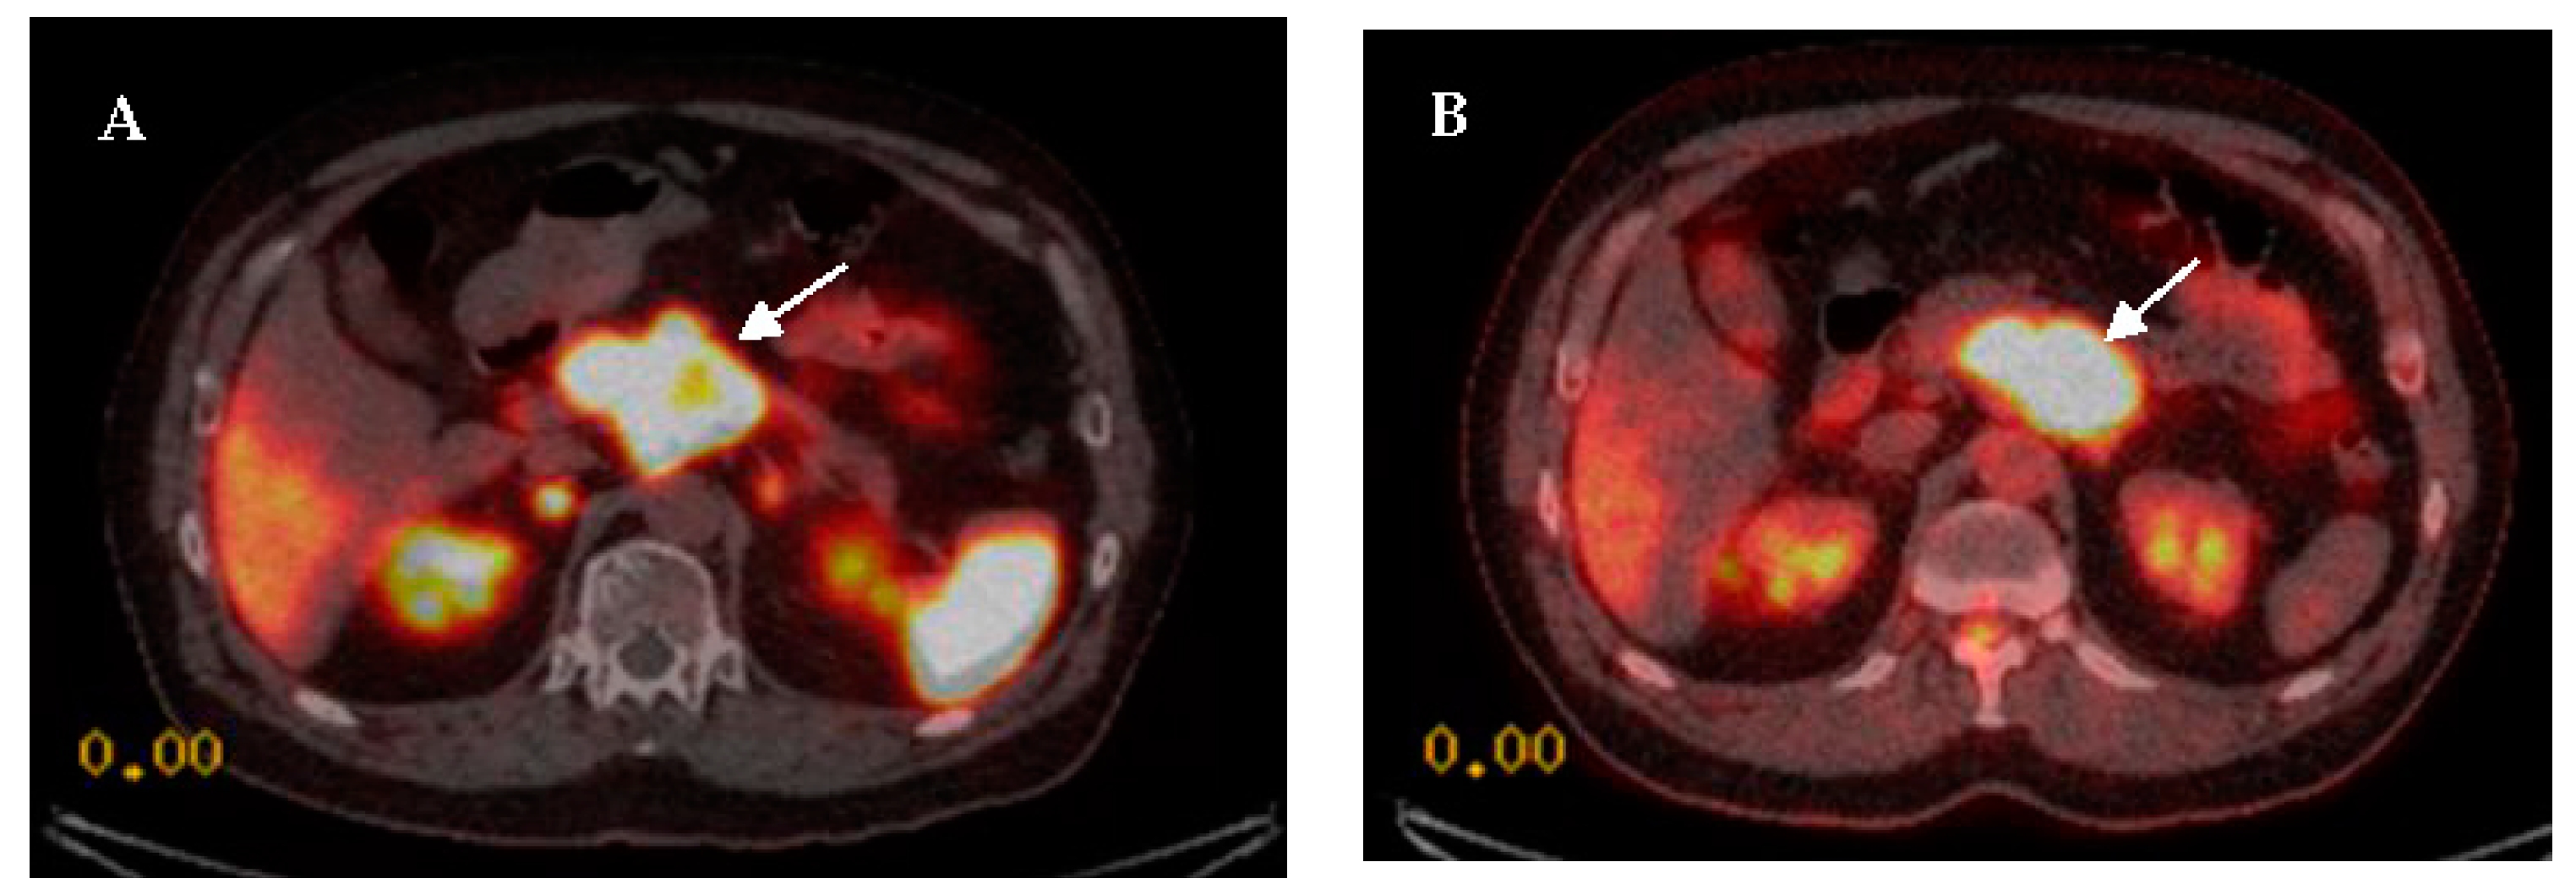

- Cingarlini, S.; Ortolani, S.; Salgarello, M.; Butturini, G.; Malpaga, A.; Malfatti, V.; D’Onofrio, M.; Davì, M.V.; Vallerio, P.; Ruzzenente, A.; et al. Role of Combined 68Ga-DOTATOC and 18F-FDG Positron Emission Tomography/Computed Tomography in the Diagnostic Workup of Pancreas Neuroendocrine Tumors Implications for Managing Surgical Decision. Pancreas 2017, 46, 42–47. [Google Scholar] [CrossRef] [PubMed]

- Partelli, S.; Rinzivillo, M.; Maurizi, A.; Panzuto, F.; Salgarello, M.; Polenta, V.; Delle Fave, G.; Falconi, M. The role of combined 68Ga-DOTANOC and 18FDG PET/CT in the management of patients with pancreatic neuroendocrine tumors. Neuroendocrinology 2014, 100, 293–299. [Google Scholar] [CrossRef]

- Muffatti, F.; Partelli, S.; Cirocchi, R.; Andreasi, V.; Mapelli, P.; Picchio, M.; Gianolli, L.; Falconi, M. Combined 68Ga-DOTA-peptides and 18F-FDG PET in the diagnostic work-up of neuroendocrine neoplasms (NEN). Clin. Transl. Imaging 2019, 7, 181–188. [Google Scholar] [CrossRef]